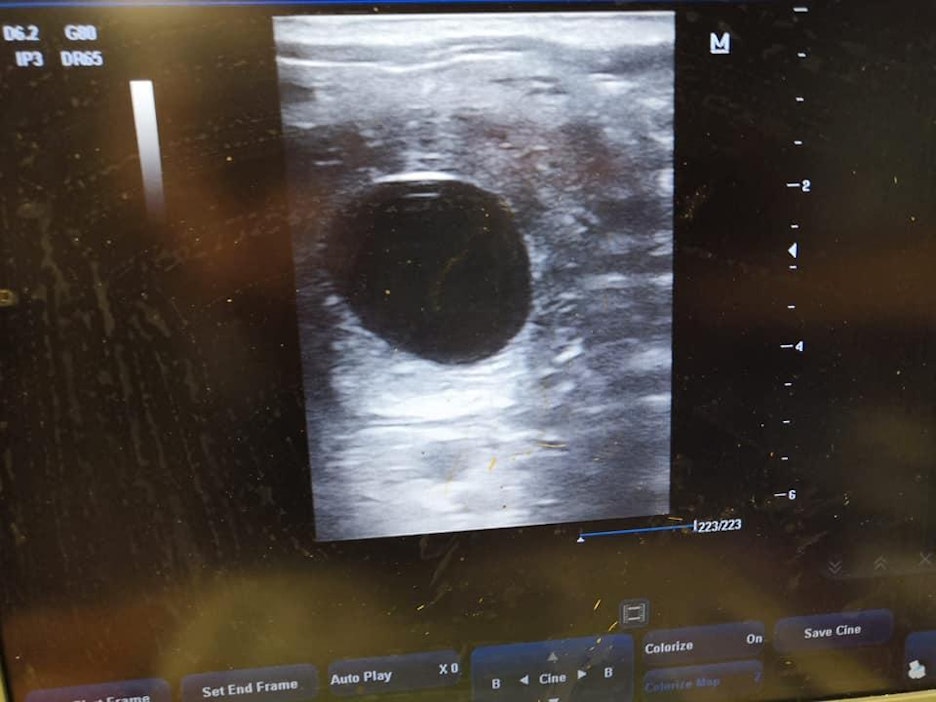

Kolmas siemennys toden sanoi: eläinlääkäri Merja-Liisa Toivonen totesi kuningattaren kantavaksi maanantain tutkimuksissa Metsäpirtissä.